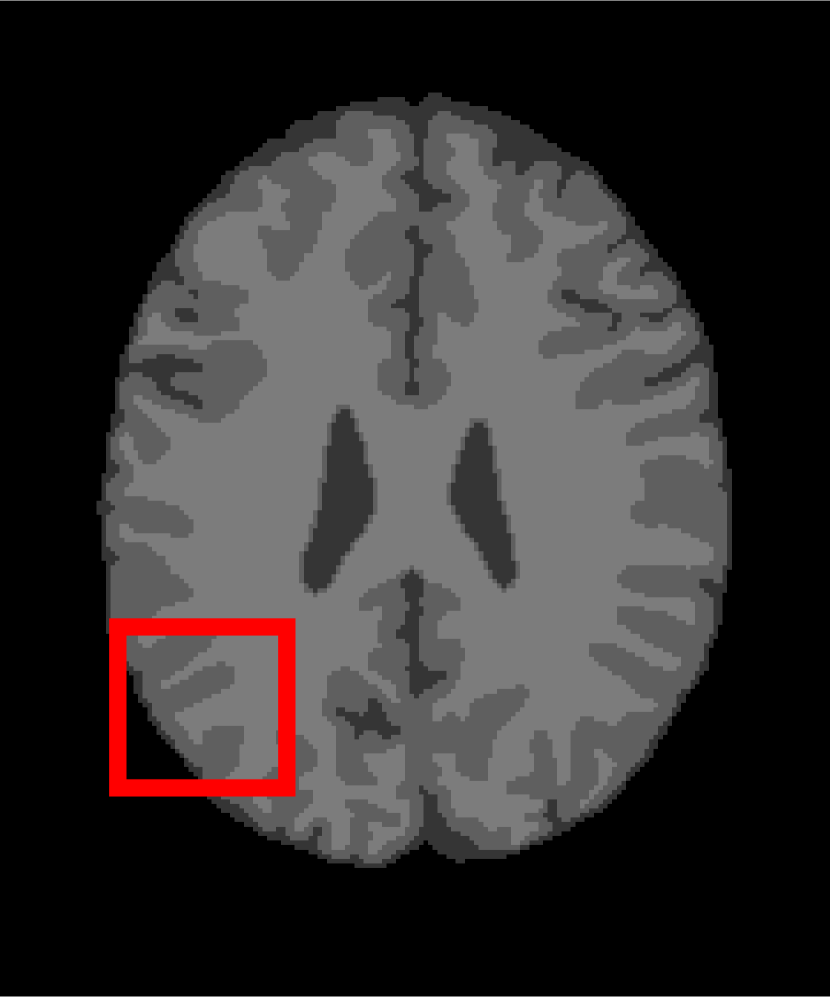

In the second experiments, we segment two medical images coming from a simulated brain database (BrianWeb): http://www.bic.mni.mcgill.ca/brainweb/. The two images are generated by T1 modality with slice thickness of 1mm resolution, 9% noise and 20% intensity non-uniformity. Here, the two images are represented two slices in the axial plane with the sequence of 100 and 110. Moreover, there are golden standard segmentations in the dataset. We set the numbers of clusters to 4. The visual comparisons are illustrated in Figs. 6 and 7.

Figure 6: Segmentation results for the first medical image. From (a) to (l): ground truth, noisy image and results of FCM_S1, FCM_S2, FGFCM, FLICM, KWFLICM, ARKFCM, FRFCM, WFCM, DSFCM_N, and LRFCM.

By focusing on the marked red square in Figs. 6 and 7, we easily find that FCM_S1, FCM_S2, FGFCM and ARKFCM are sensitive to noise. FLICM and KWFLICM are vulnerable to severe intensity inhomogeneity. FRFCM brings overly smooth results due to the use of gray level histograms. WFCM and DSFCM_N cause several contours to change. However, LRFCM acquires clear contours and suppresses noise adequately. Moreover, we find that the segmentation result of LRFCM is closer to ground truth.